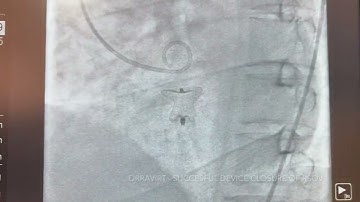

DrRaviRT - Large LV Pseudoaneurysm Device Closure